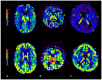

Craniosynostoses (CRS) are caused by the premature fusion of one or more cranial sutures, with isolated nonsyndromic CRS accounting for most of the clinical manifestations. Such premature suture fusion impacts both skull and brain morphology and involves regions far beyond the immediate area of fusion. The combined use of different neuroimaging tools allows for an accurate depiction of the most prominent clinical-radiological features in nonsyndromic CRS but can also contribute to a deeper investigation of more subtle alterations in the underlying nervous tissue organization that may impact normal brain development. This review paper aims to provide a comprehensive framework for a better understanding of the present and future potential applications of neuroimaging techniques for evaluating nonsyndromic CRS, highlighting strategies for optimizing their use in clinical practice and offering an overview of the most relevant technological advancements in terms of diagnostic performance, radiation exposure, and cost-effectiveness.

Keywords: arterial spin labeling; blackbone MRI; computed tomography; craniofacial surgery; craniosynostosis; magnetic resonance angiography; magnetic resonance imaging; neuroradiology; perfusion MRI.